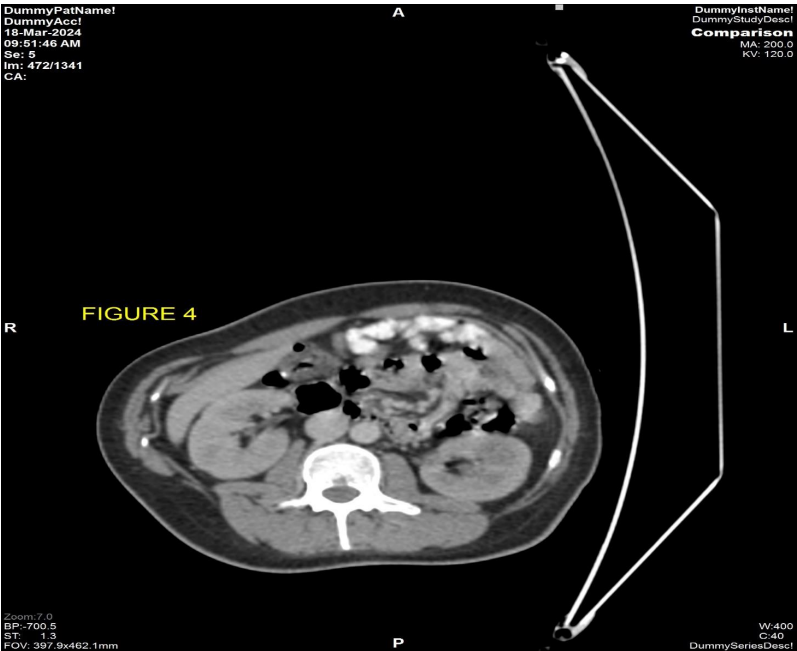

The patient underwent MRI pelvis (Fig 1 & 2) and PETCT (Fig 3 & 4) for initial evaluation (03/2024) at our institute which showed ill-defined large altered signal intensity heterogeneously enhancing mass in the right lumbar region with both intra as well as intrapelvic component by causing erosion of the right iliac bone involving the adjacent iliopsoas and gluteus muscles with central necrosis. On PET-CT scan the lesion showed significant FDG uptake with no other abnormality in the rest of the scan. Text the patient was planned for neoadjuvant chemotherapy and then for surgery. Patient took 2 cycles of neoadjuvant chemotherapy (Holoxan and Adriamycin), but after 2 cycles of chemotherapy response evaluation MRI was done (01/07/2024) (Fig 5) which showed increase in the size of lesion, so patient was planned for targeted therapy ie tyrosine kinase inhibitors, Pazopanib.

Figure 4: CT component of PETCT scan dated 03/2024 axial abdomen view shows normal small bowel wall with no obvious thickening seen.

Figure 4